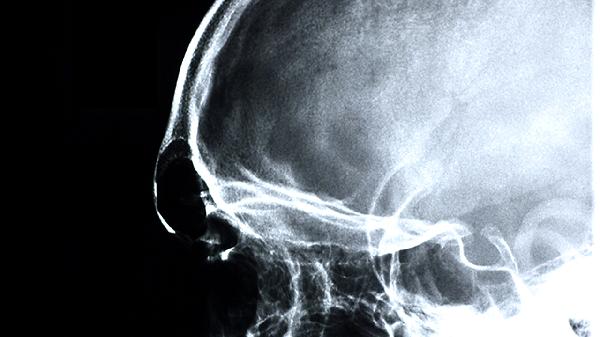

使用益智康脑丸期间应保持低盐低脂饮食,适量进行有氧运动如快走或游泳,每日保证7-8小时睡眠。避免过度用脑和情绪激动,可配合核桃、深海鱼等富含不饱和脂肪酸的食物辅助调理。若出现头痛加重或肢体麻木需立即停药并就诊,定期复查头颅CT或MRI评估脑血管状况。用药记录应包括症状变化和不良反应,复诊时向医生详细反馈。